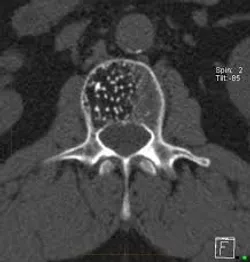

Компьютерная томография является основным методом диагностики диагностики гемангиом позвонков. Она позволяет определить размеры, распространенность, выраженность изменений костной ткани, провести дифференциальную диагностику гемангиом. Главным рентгенологическим признаком гемангиом является специфическая перестройка губчатого вещества тела позвонка, заключающаяся в сочетании частичного лизиса костной ткани с гипертрофией сохранившихся костных трабекул. На аксиальных срезах тело позвонка напоминает "пчелиные соты".